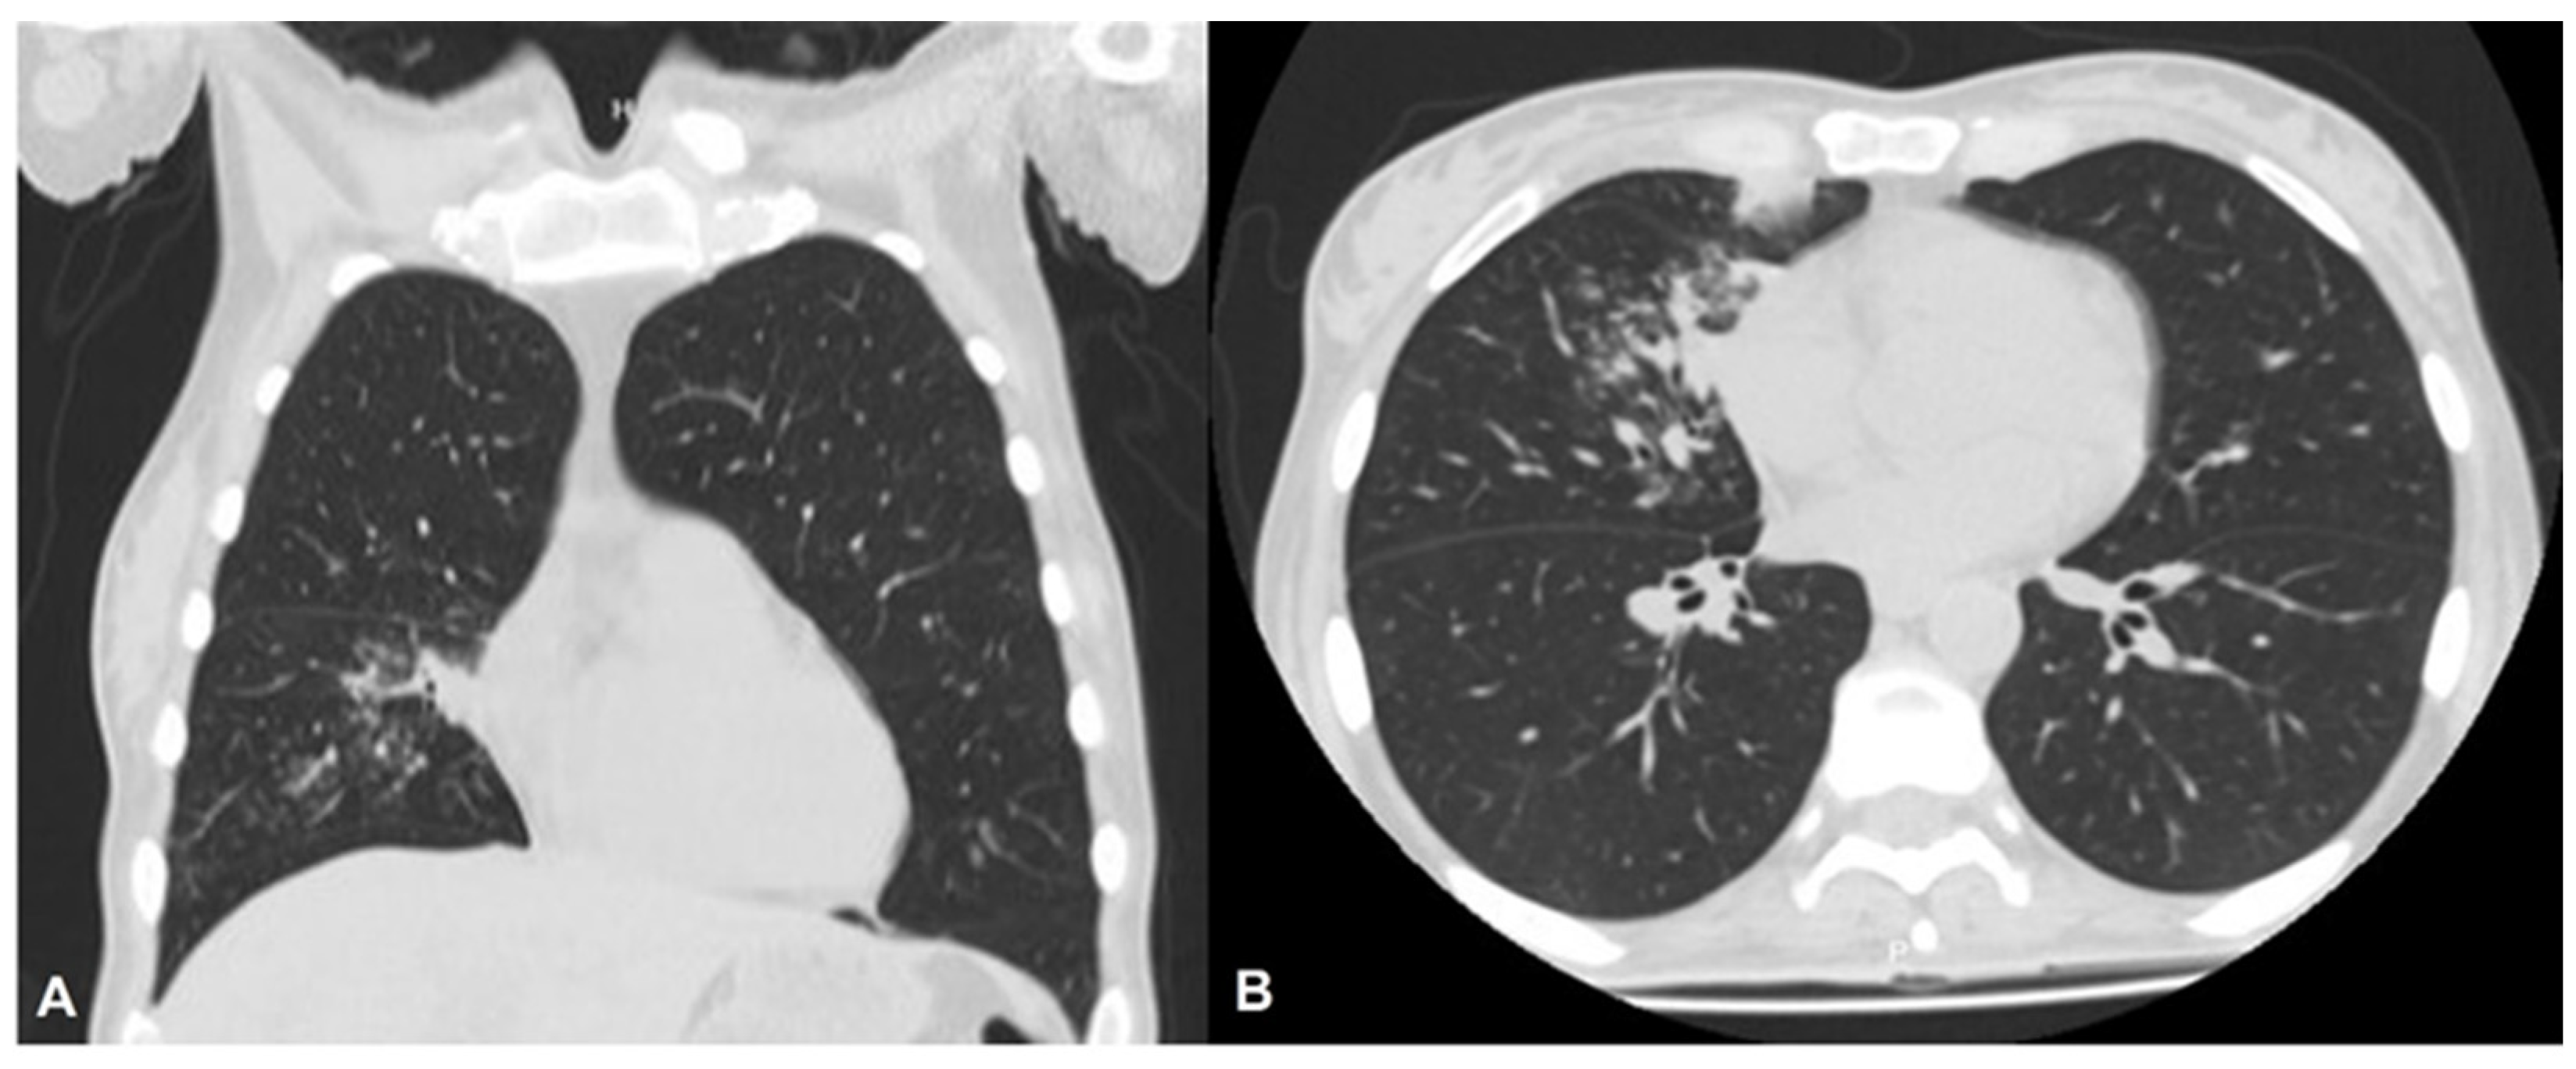

2. Case Description